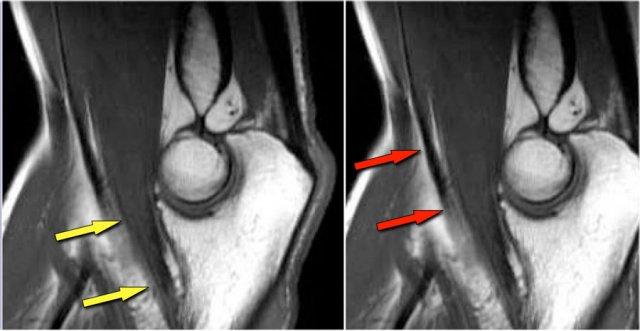

Những hình ảnh này của một cầu thủ bóng chày trẻ, xuất hiện với triệu chứng đau khuỷu tay lúc 14 tuổi.

Hình ảnh T2W-fatsat cho thấy phù tủy xương và có thể có gãy xương dưới sụn.

Rõ ràng là có người đã bảo cậu bé tiếp tục ném bóng, vì cậu quay lại ba năm sau khi 17 tuổi và bạn có thể thấy điều gì xảy ra khi người ta thúc ép quá mức để biến những đứa trẻ này thành vận động viên chuyên nghiệp.

Hình ảnh T1W cho thấy sự phân mảnh (mũi tên vàng) với một mảnh xương tự do (mũi tên đỏ).

Hình ảnh T2W chứng minh rằng mảnh xương không ổn định do có tín hiệu cao giữa mảnh xương và xương cánh tay.